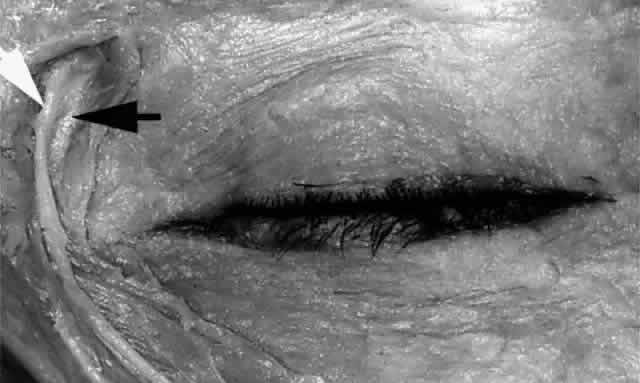

The main lacrimal gland resides in the superotemporal orbit, partially within a shallow bony fossa in the lateral angular process of the frontal bone (fossa glandula lacrimalis). The gland is situated between the eyeball below and the curved orbital wall above, giving it a somewhat compressed and curved shape. It may extend inferiorly to the lateral canthal tendon. The lateral horn of the levator aponeurosis crosses the gland anteriorly, separating it into a larger superior or orbital lobe and a smaller inferior or palpebral lobe (Fig. 2). The division is incomplete because the larger orbital lobe is connected to the smaller palpebral lobe posteriorly by a bridge of glandular tissue, draining tubules, and Müller's muscle, which is attached to the underside of the levator muscle and aponeurosis. The lacrimal gland is surrounded by fibrous tissue that is attached superiorly to the periosteum of the frontal bone and inferiorly to the orbital portion of the zygomatic bone.1

Fig. 2. With the roof and lateral wall of the left orbit removed, this cadaver dissection demonstrates the orbital lobe (black arrow) and the palpebral lobe (white arrow) separated by the lateral horn of the levator aponeurosis (pointer).